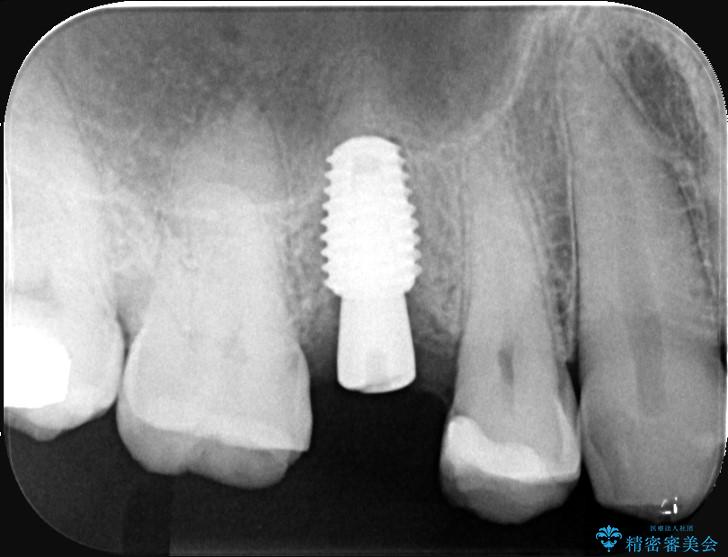

右上5番が根尖性歯周炎と歯周病が同時に併発しており、骨が大きく溶け、歯の動揺も著しかったため保存困難と判断をし抜歯してインプラントで治療を行いました。

インプラントはインプラント周囲炎になりにくいスクリュータイプを使用しています。